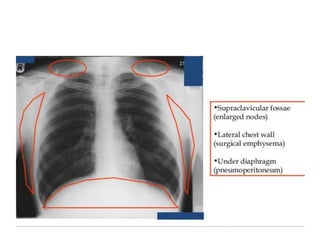

This document provides an overview of interpreting chest x-rays and identifies several key factors. It discusses the importance of inspiration, penetration, and rotation in obtaining a technically quality radiograph. It also outlines different views of chest x-rays including PA, AP, and lateral views. Finally, it identifies several anatomical structures that should be evaluated when interpreting a chest x-ray such as the lungs, heart, diaphragm, bones, and soft tissues.